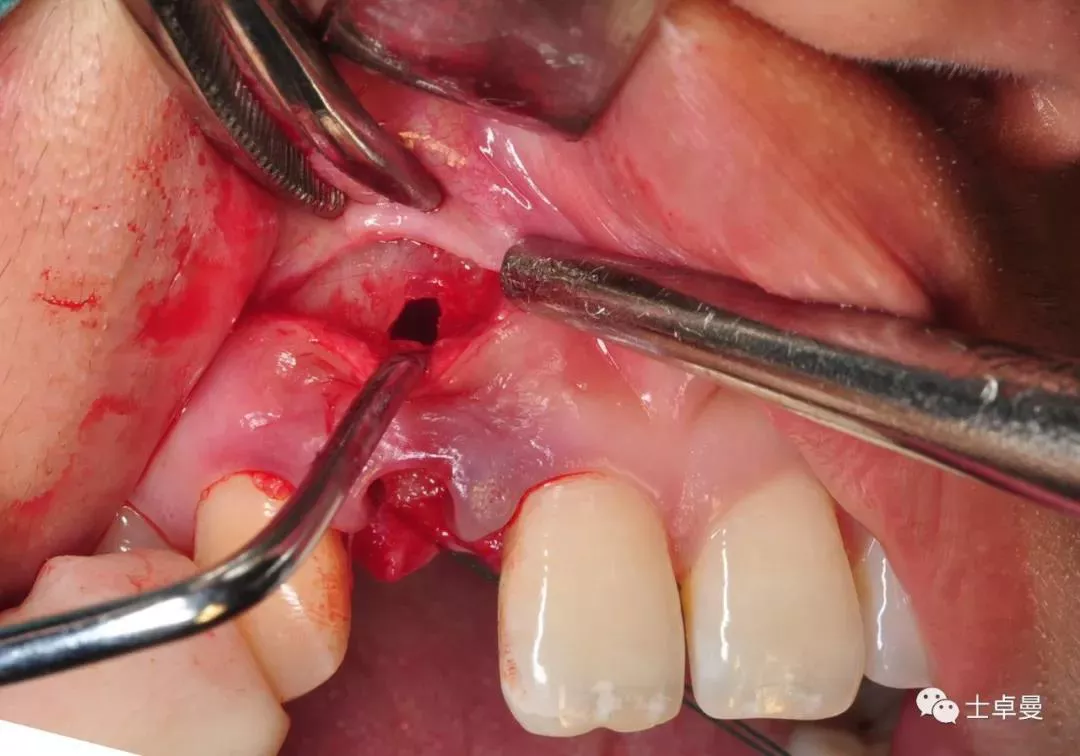

·       根尖穿孔区局部翻瓣,暴露穿孔部位;

根尖穿孔区翻瓣

周围皮质骨增加血运营养孔

偏腭侧植骨种植体

唇侧骨板下1mm

唇侧跳跃间隙大于2mm

·      放置骨粉、骨膜;

根尖区局部植骨

覆盖胶原膜